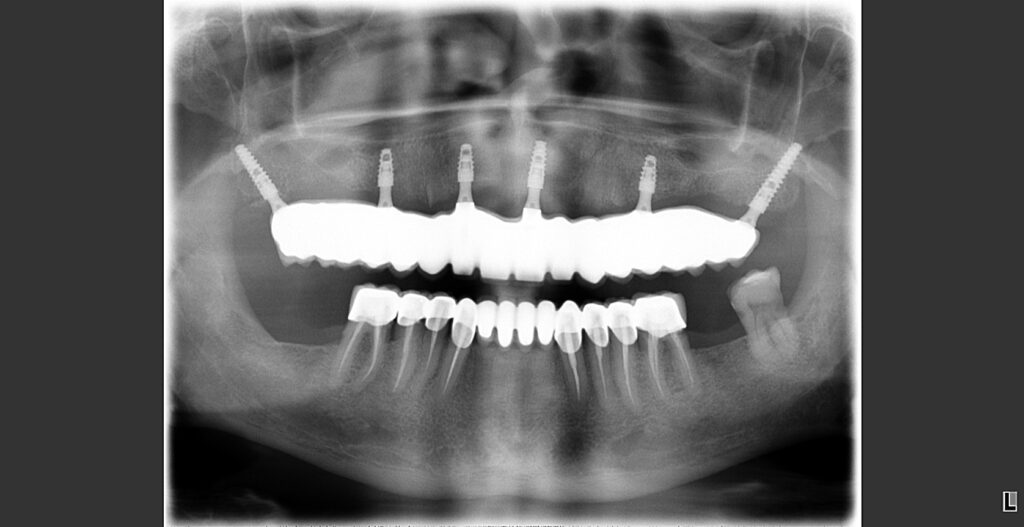

A dental implant acts as a replacement for damaged roots and provides support for a replacement tooth, denture or bridgework (in combination with additional implants). The implant fuses with the existing bone to create the basis for additional dental work. Titanium implants are most commonly used, following on from techniques developed by Professor Per-Ingvar Branemark. […]

An overdenture is a type of denture that is secured by precise dental attachments. The attachments are placed in the tooth root, or dental implant, which have been placed specifically for the overdenture attachment. Types of overdentures include bar joint dentures and telescopic dentures. If you lose most, or all, of your lower teeth there […]

Susan had Ankylos Implants, zirconium crowns and dental hygiene (upper+lower jaw). She stayed in one of our apartments for a couple of days. Please visit https://seashell-hare-375411.hostingersite.com to make a free 30 second inquiry and receive your free quotation within 24hrs. Or simply call Daniel Shaw on 00421 915 892 218 for more details. Check out […]